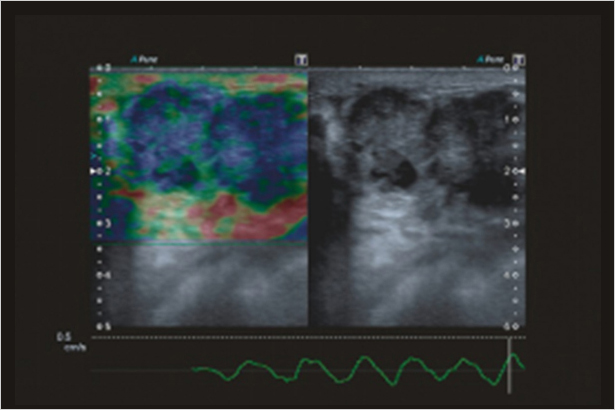

全方位的具有原始數據功能的彈性解決方案幫助您定位并評估淺表占位,準確性高,敏感度高,效率高,適用于不同臨床應用。在圖像中彩色編碼組織彈性的不同程度,使可疑組織可視化